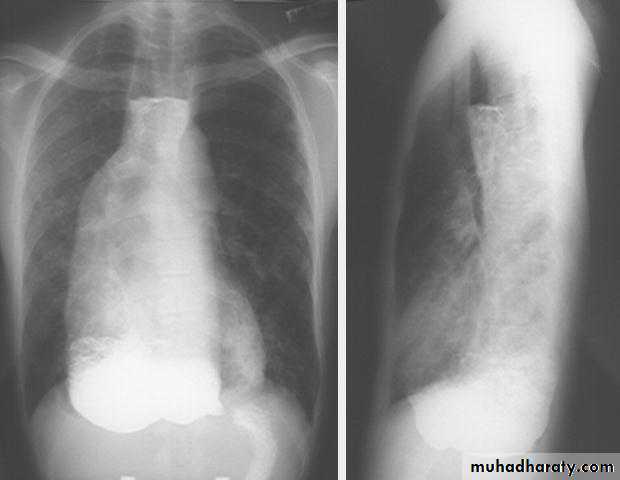

Investigations Chest X-ray; widening of the mediastinum, aspiration pneumonia.A barium swallow; tapered narrowing of the lower esophagus, esophageal body is dilated, aperistaltic and food-filled.Endoscopy; must always be carried out, carcinoma of the cardia can mimic the presentation and radiological and manometric features of achalasia ('pseudo-achalasia').Manometry; confirms the high-pressure, non-relaxing lower esophageal sphincter with poor contractility of the esophageal body.